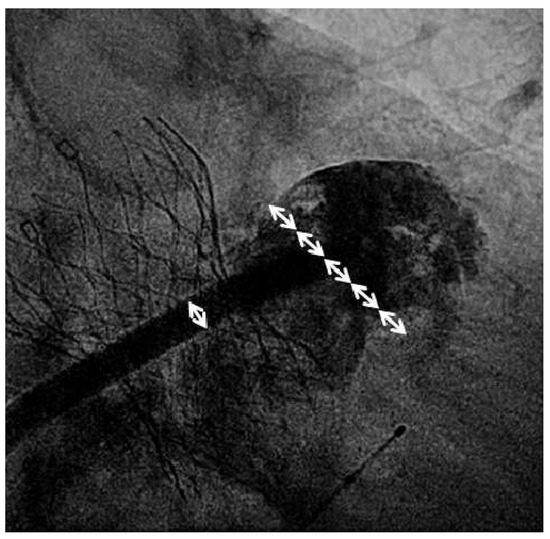

Due to his age and his metastasising prostate cancer, the patient refused to undergo open-heart surgery. Technical eligibility for transcatheter valve implantation was therefore evaluated. The angiography showed that the peripheral arteries were large enough for a transfemoral procedure, in that they could accommodate an 18French sheath. Annulus sizing was performed by CT-angiography revealing sinuses of Valsalva of 41 mm, a mean annulus diameter of 31.5 mm (min. 26 mm, max. 37 mm), a perimeter of 102 mm and an annulus area of 720 mm2. The largest device currently available is the 31 mm CoreValve prosthesis with a device area of 755 mm2 and a perimeter of 97 mm. For the use of this valve type, a maximum annular area of 660 mm2 and a maximum perimeter of 91 mm to achieve reasonable 7–14% over-sizing is recommended. Despite the above-mentioned measurements on CT, it was decided to proceed with balloon-sizing of the annulus based on the angiographic impression (suggesting feasibility of TAVI) and if this showed good sealing to proceed ad-hoc with the valve implantation. The procedure was performed with local anaesthesia and with fluoroscopic guidance only. An 18French Cook sheath (Cook Medical Inc., Bloomington, USA) was introduced via the right femoral artery after preclosure with two Perclose ProGlides (Abbott Vascular, Abbott Park, USA). Balloon-sizing was performed using a 26-mm Z-Med Balloon (NuMED Inc., Hopkinton, USA). Aortic balloon sizing was performed under rapidpacing using simultaneous contrast injection to the aortic root. Minimal aortic regurgitation was seen during valvuloplasty and the decision was taken to pursue with implantation of a CoreValve 31-mm prosthesis (Medtronic, Minneapolis, USA). After valve implantation, a large pulse-pressure and a high left ventricular end-diastolic pressure were evident. Reusing the 26-mm Z-Med balloon, a postdilatation was performed which improved haemodynamics (LVEDP 13 mm Hg, diastolic blood pressure 43 mm Hg, systolic blood pressure 106 mm). The final aortogram showed mild aortic regurgitation.

Figure 1. Fluoroscopic sizing of the left atrial appendage (LAA) landing zone: the outer diameter of the 14F sheath measures 5.4 mm (single white arrow). The device landing zone measured approx. 23 mm (almost 4.5x the outer diameter of the sheath; serial white arrows). Therefore, a 28 mm device was chosen.